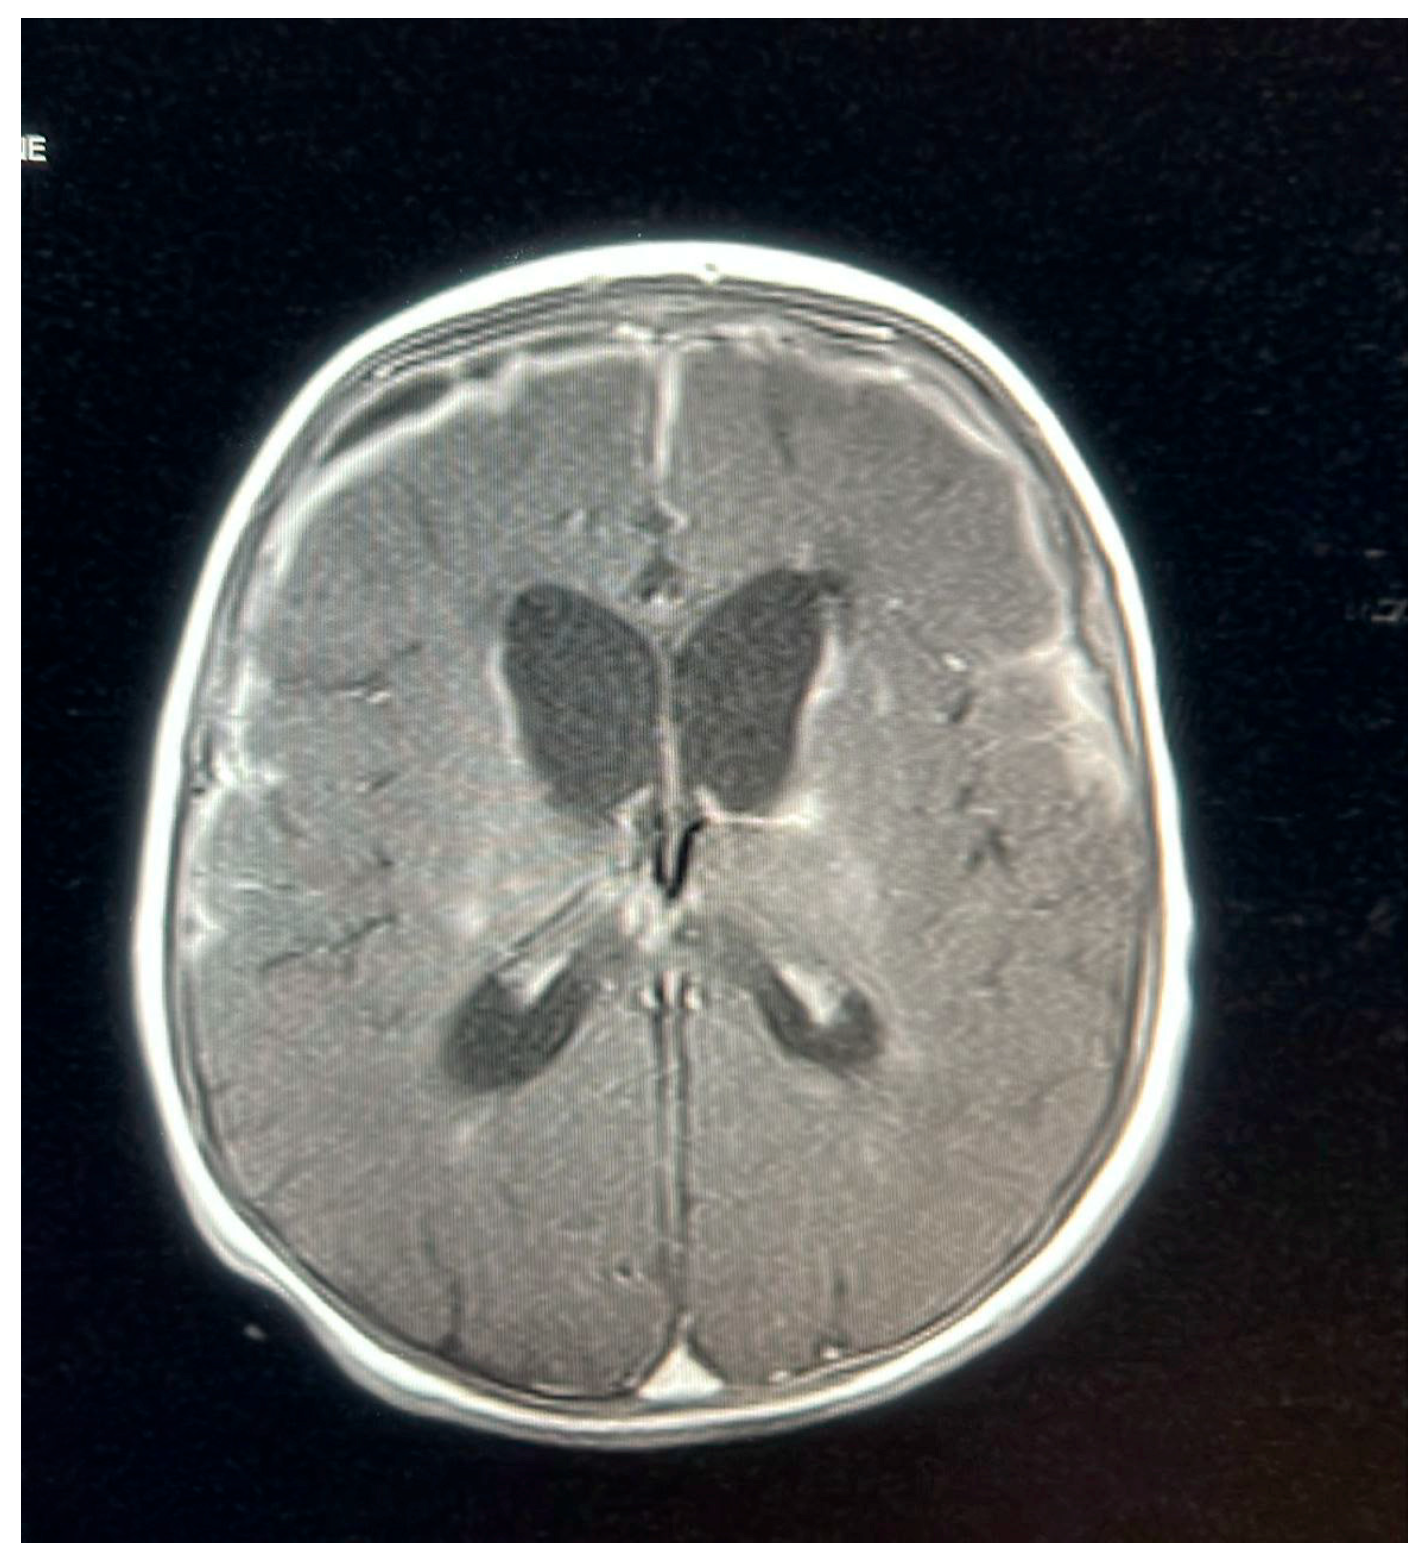

A follow-up MRI on 9 October 2022, 2 weeks later, showed new subdural empyemas and worsening meningitis. The small abscess-like lesions near the ventricles had grown slightly compared to the earlier scan. Signs of previous hypoxic–ischemic injury were observed, with some improvement, including reduced swelling and improved blood flow in the periventricular white matter and posterior parietal lobes. The basal ganglia lesions could represent small abscesses, brain infection (cerebritis), or subacute strokes. The neurosurgical team determined that the patient did not require surgical intervention, as the empyema was not causing a mass effect and the patient remained clinically stable. The patient was continued on meropenem for 6 weeks, as a second MRI and after 2 weeks of proper treatment showed new collections, while ganciclovir was discontinued after the patient received 21 days of treatment.

An MRI repeated on 11 November 2022, after 7 weeks of treatment, showed interval resolution of the abscesses and subdural empyema, with resolution of leptomeningeal disease. Expected changes were observed, including brain volume loss and periventricular leukomalacia, with the previously described foci of enhancement. The internal auditory canals appeared unremarkable (Figure 1, Figure 2, Figure 3, Figure 4 and Figure 5).

Figure 3. MRI brain scan showing worsening of leptomeningeal enhancement.